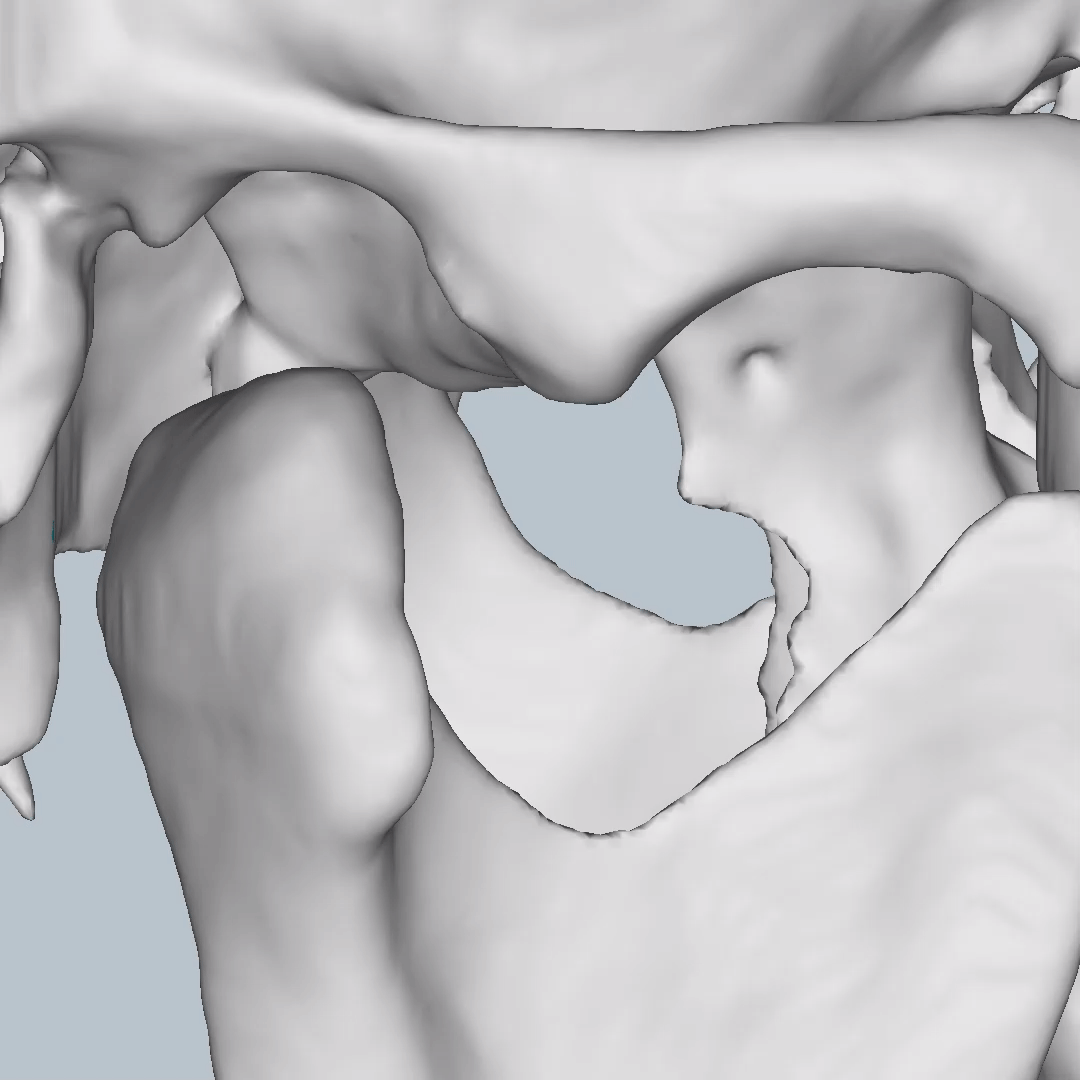

Cross-sectional and coronal views of teeth show torque and buccolingual relationships such as crossbite.

TMJ coronal/sagittal slices and summations visualize abnormal positioning/shape of the mandibular condyle.

The orthodontic report generates OPG and front/lateral cephalograms. These are not as sharp as true OPG and cephalograms. Tracings of the maxilla, mandible, central incisors, canines, and molars are automatically produced on the generated frontal/lateral cephalogram.

I showed the orthodontic report to an orthodontist colleague. She found the tracings to be fairly accurate compared to a real lateral cephalogram of the same patient. She did further tracings on the generated lateral ceph and advised it was difficult to visualize points such as Nasion, ANS, A Point, Condylion, and Orbitae and visualize the fourth vertebrae to determine peak growth phase. Furthermore, other orthodontic software can automatically calculate skeletal/dental relationships, planes, and angles.